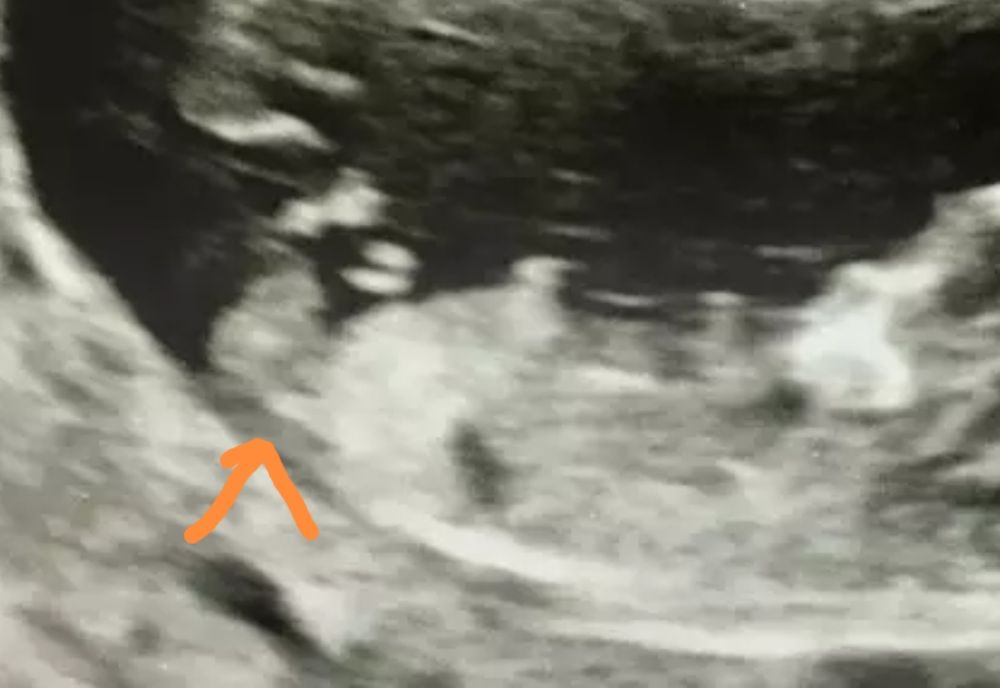

А это разве не бугорок? Если это он, то девчуля у вас😍

Мария //рожу дочку в 2021//, ого, даже не обратила внимания) он как бы за ногой, но узи видит?

Elle Light, просто полового бугорка торчащего не вижу))А по очертаниям предположила бы мальчика)